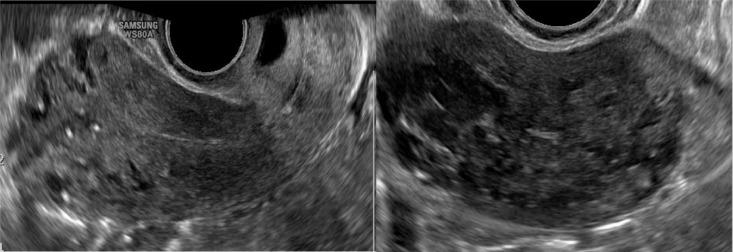

Uterine arteriovenous malformation (AVM) is a rare condition that may lead to a life-threatening state. The urgency of diagnosis and treatment for uterine AVM should be emphasized. This case report describes a 42-year-old woman with a vaginal hemorrhage. In the previous month, the patient also had a hemorrhage after induced abortion that required a bilateral artery suture hemostasis of the uterus. On ultrasound, there was a lesion suspected by acquired AVM. Magnetic Resonance Angiography and Digital Subtraction Angiography was indicated to confirm the diagnosis. The patient was successfully treated by uterine artery embolization. After 6 months, the re-examined result showed no lesion of AVM.

Color Doppler US in the evaluation of uterine vascular abnormalities.彩色多普勒超声在子宫血管异常评估中的应用

Radiographics. 2002 Jan-Feb;22(1):47-53. doi: 10.1148/radiographics.22.1.g02ja0947.